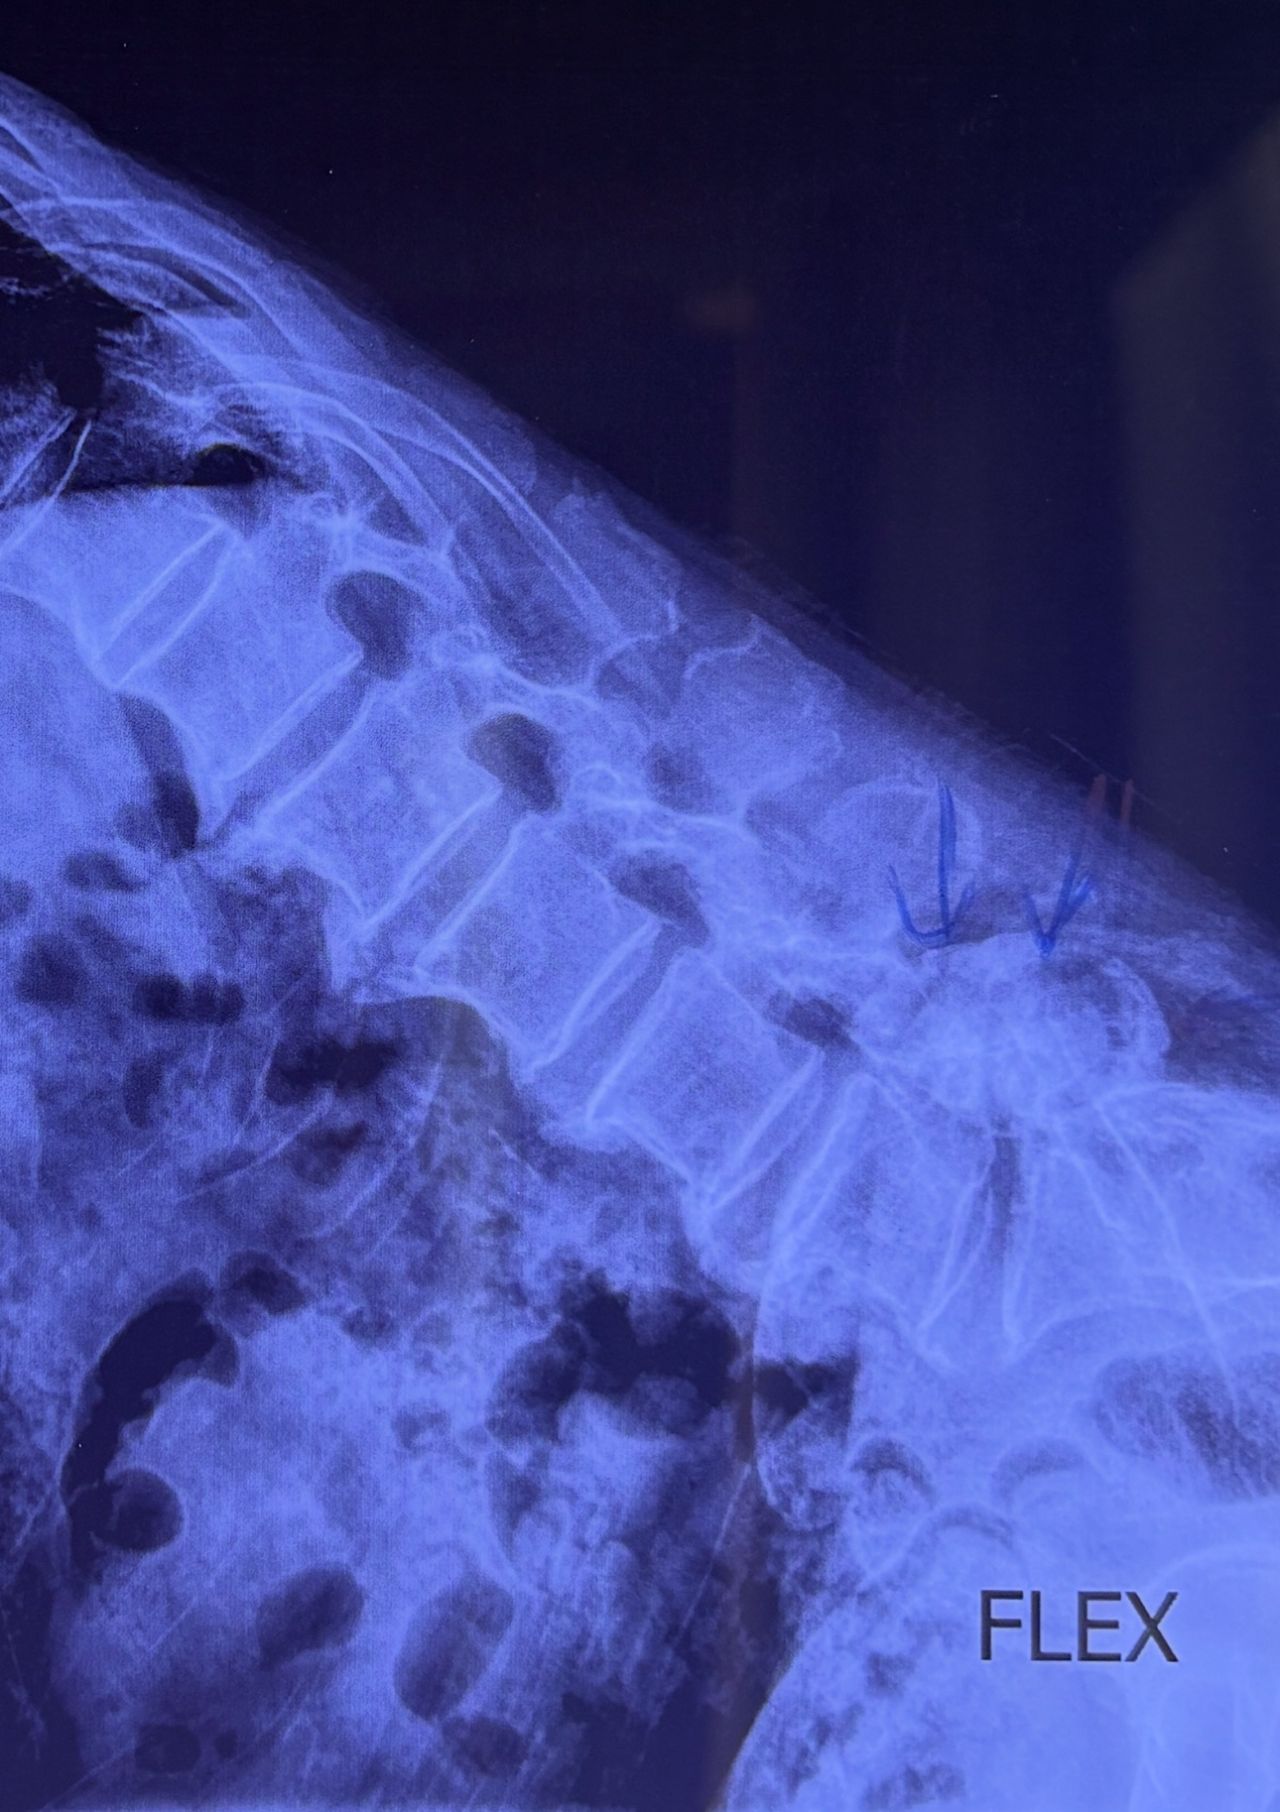

L4-L5 level:

sever L4-5 canal stenosis mainly due to FL hypertrophy?

CSF block. Mild L3 retrolisthesis, facets hypertrophy bilateraly causing L and R IVF stenosis, disc hyperbule

Since I’ve noticed instability in some segments I asked for dynamic L/S x ray:we see mild L4 ant listens due to DjD/DDD. There is not any pars defect.